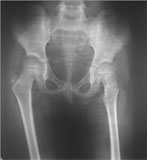

The x-ray picture here shows the antero-posterior projection of pelvis with both the hips and sacro-iliac joints. The left hip appeared as is seen in lateral view – the lesser trochanter is not visible and the greater trochanter is overlapping the neck of femur. |